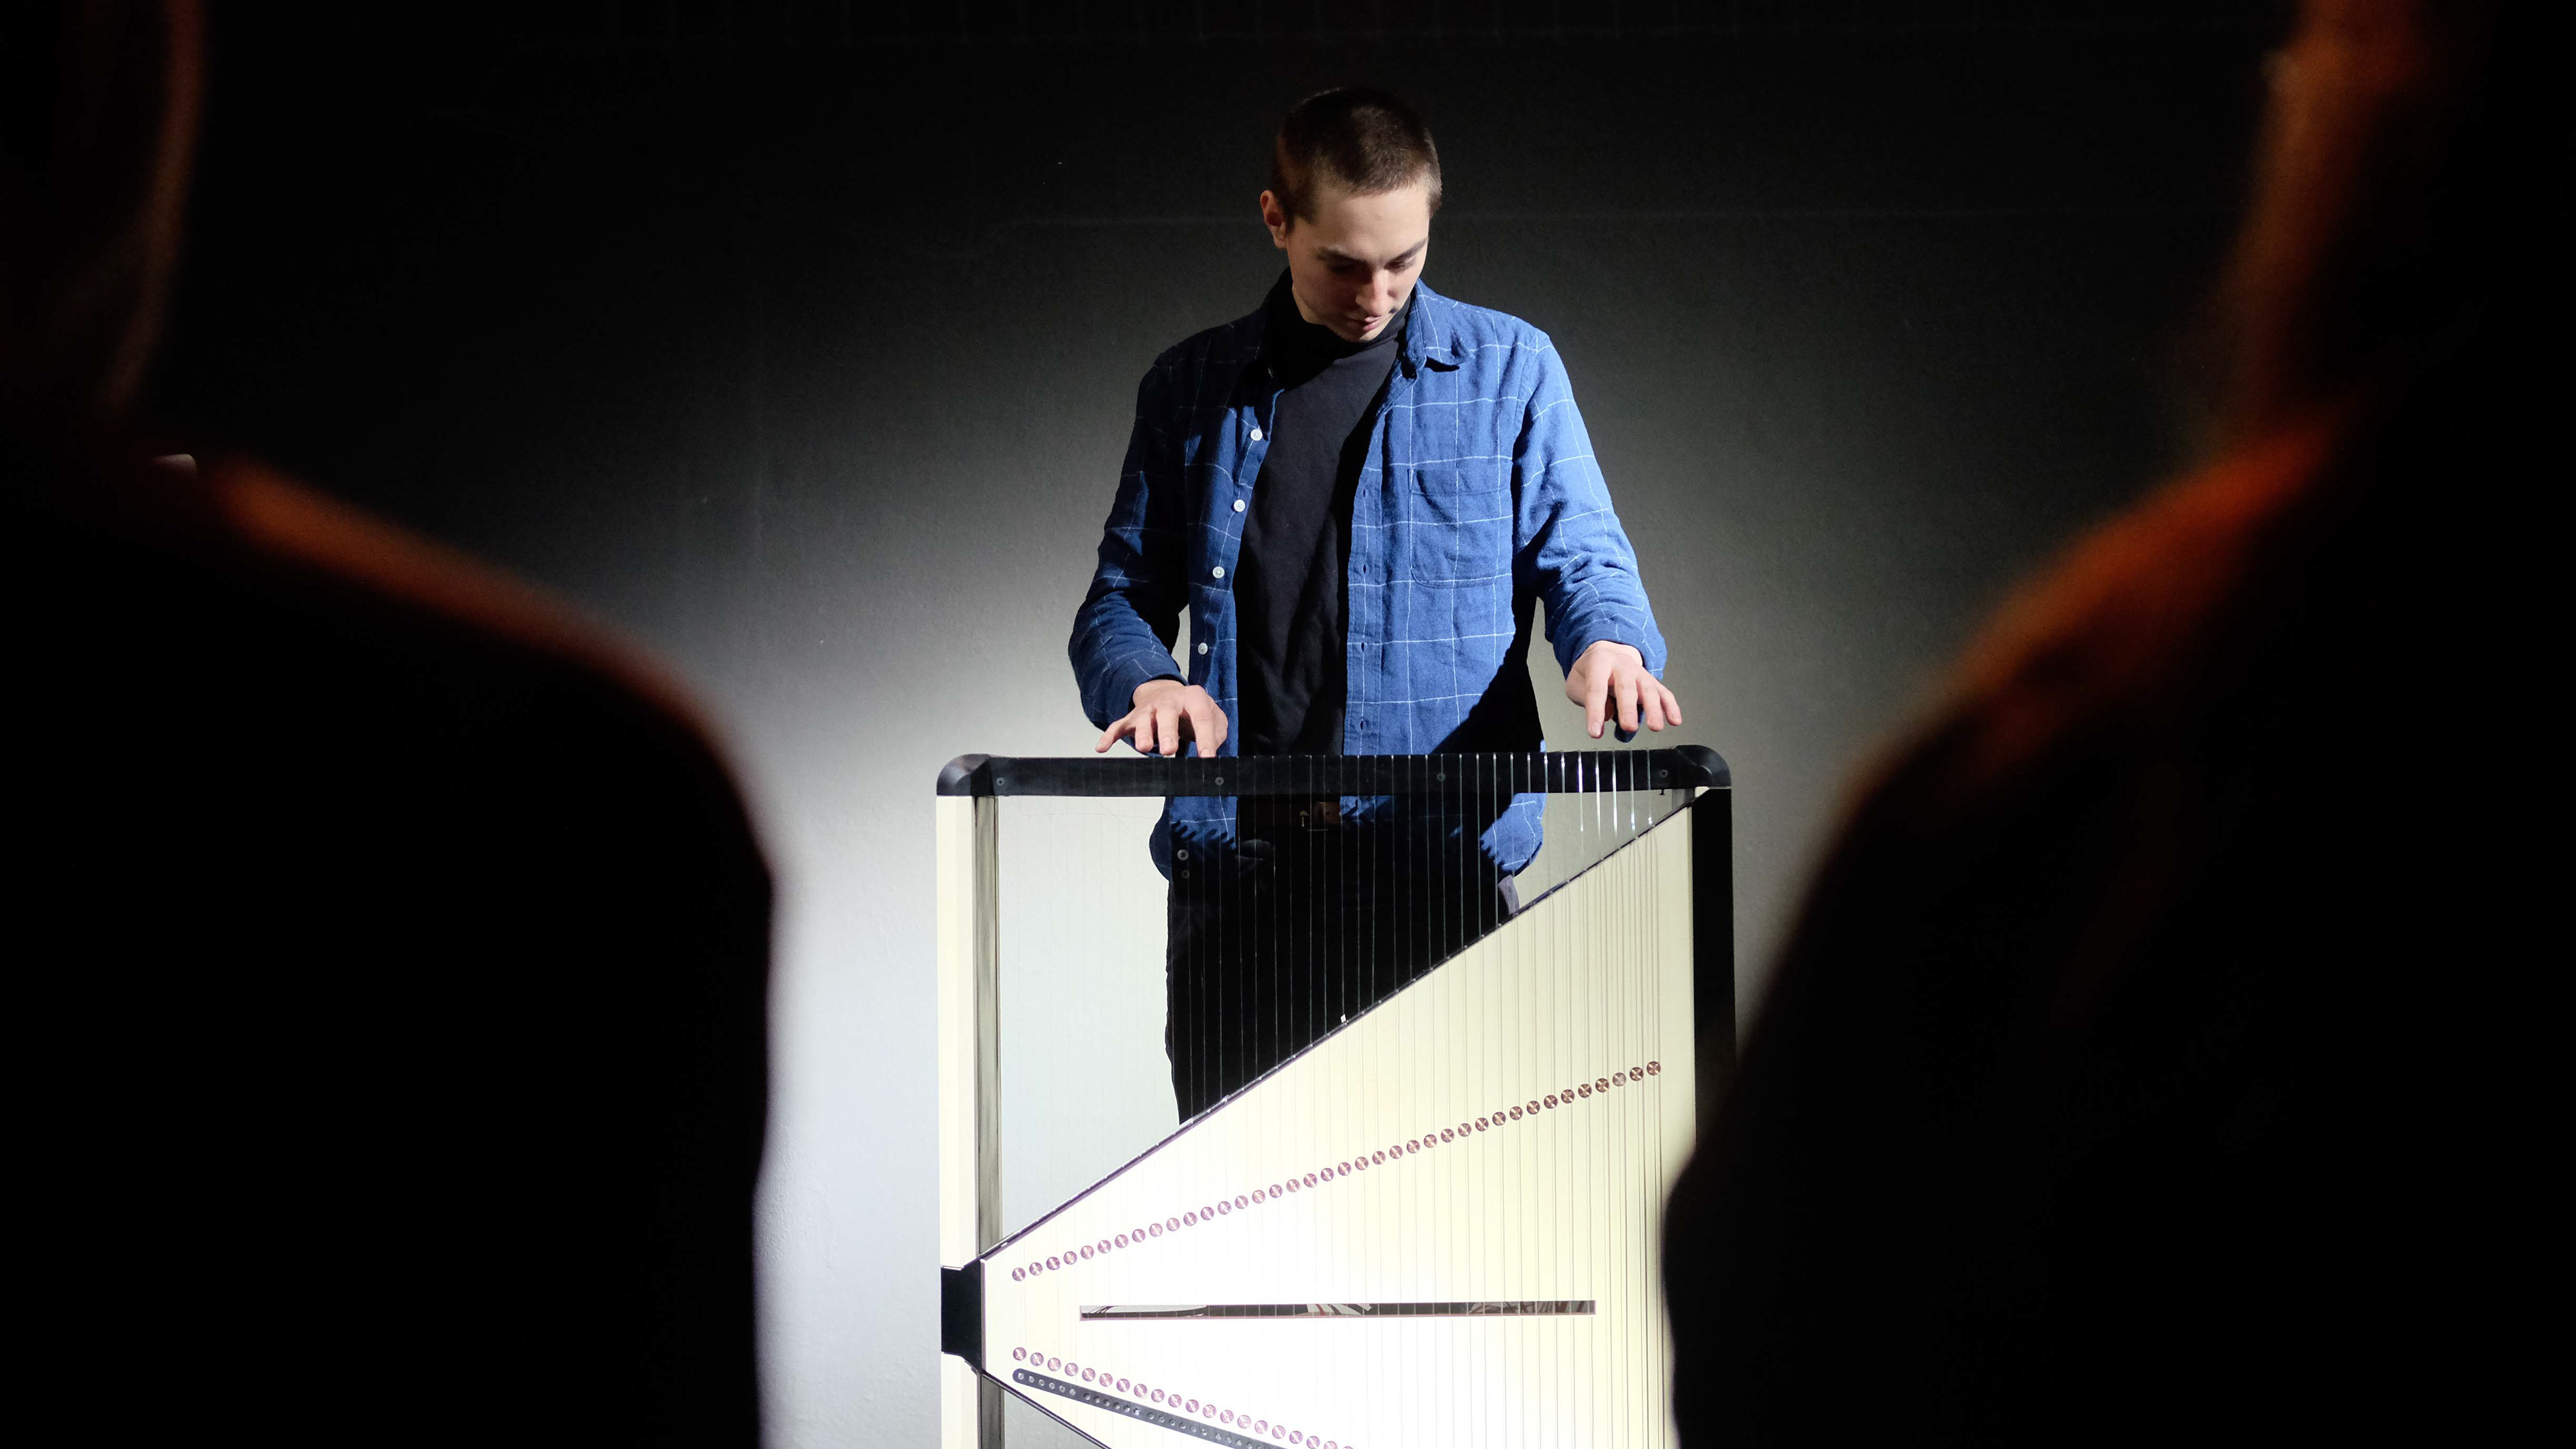

The central design feature is the hexagonal gantry opening. It provides space for the lamps and displays. The large fronts of the gantry offer space for a display of different coloured patterns and animations, which visualize the radiation. These can be individually selected and adapted together with the overall height of the gantry. The patterns pick up on the hexagonal shape of the gantry opening and set it off. To protect the interventionists from radiation, lead glass panels and a radiation protection tray are installed. The sliding lead glass panels allow individual adaptation to the patient and the interventionists working space. The tray serves to protect the abdomen and offers a lot of foot space as well as a front leaning aid for a safe stand.

Due to the new position and height of the gantry opening, the isocenter is shifted upward compared to conventional CT units. In order for the physician to operate as usual in the isocenter, his platform must also be shifted upward by this height difference. A review in VR showed that a platform height of 15cm provides the optimal comfort for the interventionalist.

Various tables can be suspended on the railing. This enables the individual positioning of surgical instruments and devices. To relieve the interventionists, it is also possible to lean against the railing, similar to a standing seat in a gondola or tram. In addition, the railing offers protection against a potential fall from the platform.